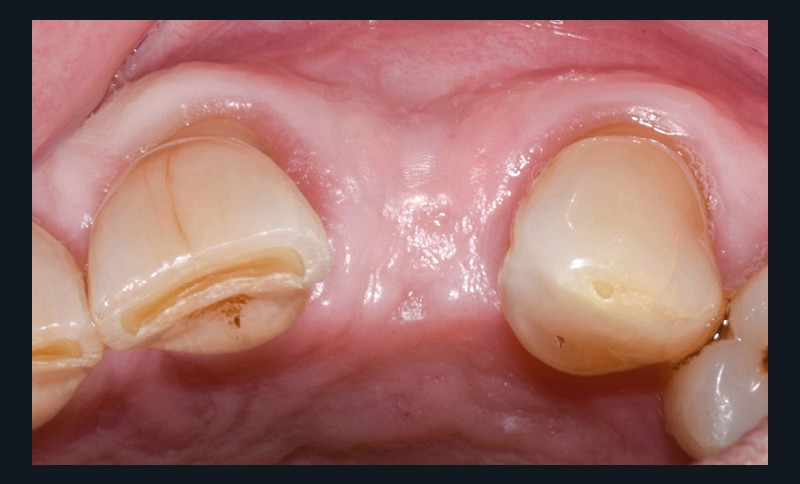

Un patient de 62 ans se présente en consultation afin de réaliser les coiffes prothétiques des dents 12 et 22. La 12 présente une restauration par prothèse transitoire non adaptée. Un implant au niveau de la 22 a été posé par un autre praticien selon une technique chirurgicale en deux temps. Le praticien a adressé le patient pour la réalisation prothétique. L’option de bridge collé cantilever mono ailette n’avait pas été retenue ou proposée selon une technique chirurgicale en deux temps. Le patient souhaite rétablir l’esthétique et la fonction de ces deux dents uniquement.

Au vu des conditions initiales, il nous apparaît impossible de restaurer une esthétique satisfaisante, notamment au niveau de l’alignement des collets, sans une chirurgie muco-gingivale associée à une réhabilitation des dents antérieures par facettes. En effet, la perte de la 22, associée à une forme triangulaire des dents, a provoqué un non-alignement des collets ainsi que la présence de trous noirs entre les dents 21-22 et 22-23. Cependant, les contraintes exprimées par le patient contre-indiquaient ce traitement.

La proposition thérapeutique retenue par le patient est donc une réhabilitation par couronne céramique sur 12 (dento-portée) et 22 (implanto-portée). Ce choix thérapeutique impose de concevoir des dents qui s’intègrent au mieux dans l’harmonie du sourire, tout en étant conscient des limites d’un tel traitement.